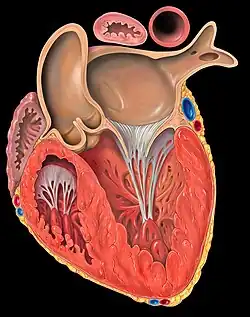

Corte transversal de corazón humano que muestra la aurícula izquierda y el ventrículo del mismo lado. | ||

La aurícula derecha recibe la sangre carboxigenada que proviene de las venas cavas superior e inferior, tras haber recorrido el organismo. A través de la válvula tricúspide pasa esa sangre al ventrículo derecho, el cual a su vez la bombea hacia la arteria pulmonar a través de la válvula pulmonar. En los pulmones, esa sangre se oxigena y regresa al corazón a través de las venas pulmonares, que desembocan en la aurícula izquierda. A través de la válvula mitral, esta sangre pasa al ventrículo izquierdo y, desde allí, a través de la válvula aórtica, a la aorta, desde donde se distribuye a todo el organismo.